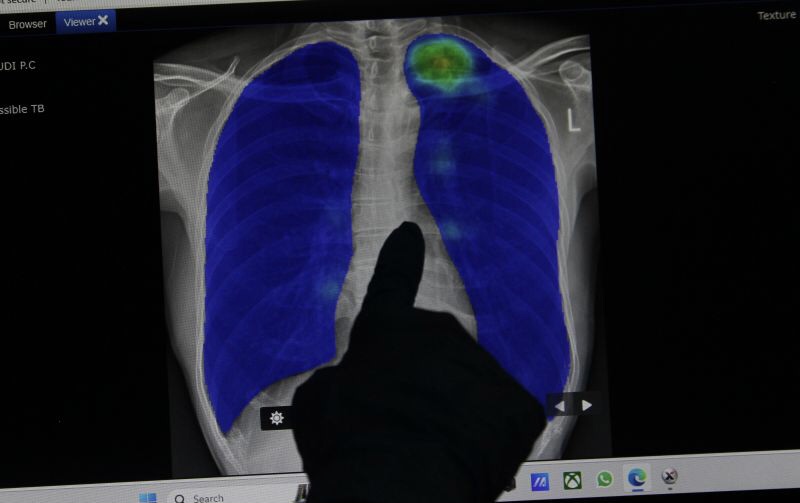

Jakarta (gokepri) – Dokter Spesialis Paru dari Rumah Sakit Umum Pusat (RSUP) Persahabatan Jakarta dr Faiza Hatim SpP mengimbau masyarakat mewaspadai bahaya tuberkulosis (TB/TBC) laten yang bisa timbul tanpa gejala.

TBC laten merupakan kondisi dimana sistem pertahanan tubuh tidak mampu mengeliminasi kuman TBC secara sempurna, namun sistem pertahanan tubuh mampu mengontrol sehingga kuman yang menginfeksi seperti tidur, dan bisa bangkit kembali saat daya tahan tubuh melemah.

Untuk itu, ia mengimbau masyarakat yang memiliki kontak erat dengan pasien TBC untuk memeriksakan diri ke puskesmas terdekat, guna menjalani pemeriksaan tuberkulin, untuk mengetahui adanya TBC laten dalam tubuh, agar penanganan penyakit tersebut bisa dengan segera.